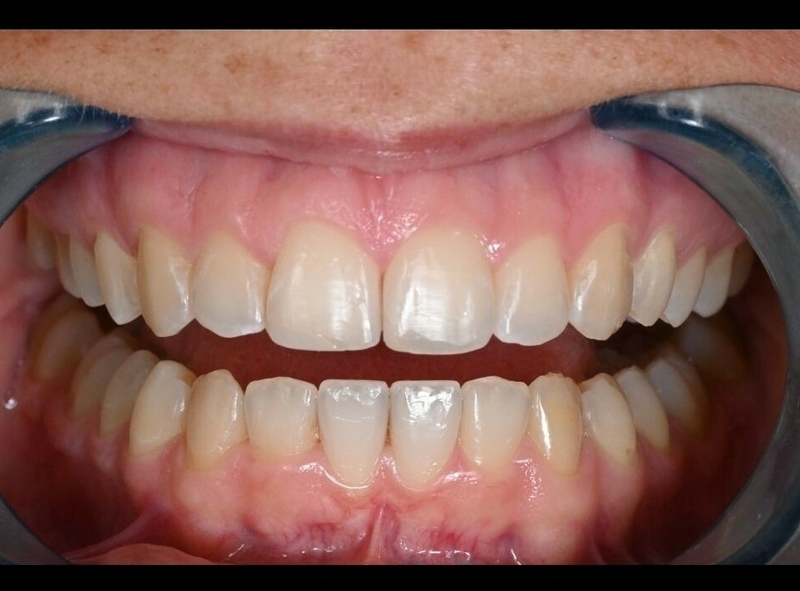

Avant

Après